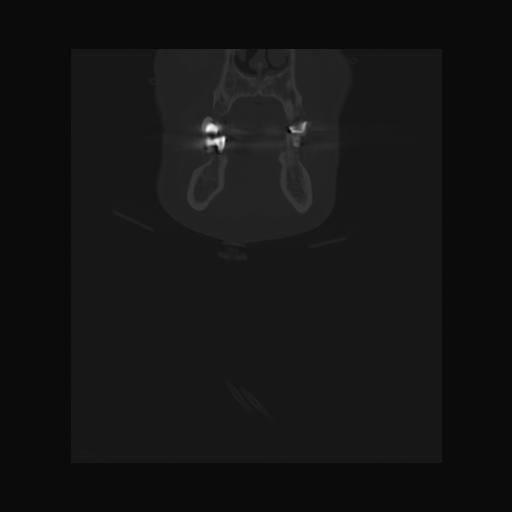

16 HUESO,,Coronal,2.000,HUESO,Coronal,